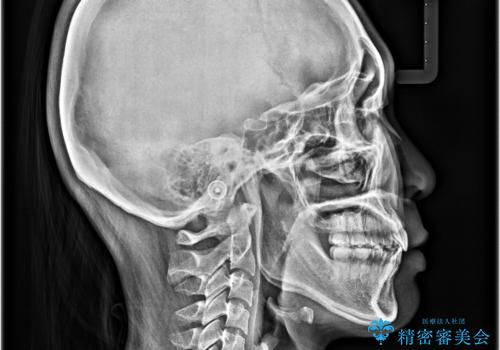

- 全体的なデコボコと口元の突出感を改善したいとのことで来院された患者様です。

このままデコボコを整えるとさらに突出感が増すため、上下左右の第一小臼歯を抜歯し、ワイヤー装置にて矯正しました。

結婚式で途中装置を外した時期がありましたが、2年で治療を終えることができました。